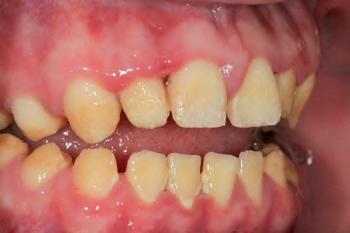

The patient was an 18-year-old male with a confirmed family history of Xlinked AI, who was otherwise in good health and non-smoking. Upon initial clinical presentation, a low-caries-risk, complete adult dentition from second molar to second molar was present, which was globally affected by pitted, hypoplastic and hypomineralised AI, dento-alveolar disproportion and an unusual generalised open occlusion, characterised by one occlusal contact at the right first molar region in the maximum intercuspation position (MIP). Historical paediatric management of the dentition involved placement of stainless steel crowns at the first permanent molar sites to protect the emerging dentition from post-eruptive breakdown and loss of occlusovertical dimension during the mixed dentition phase.6 On adult presentation, all but the UR6 stainless steel crown remained intact. Oral hygiene was poor, with evidence of plaque-induced chronic gingivitis (Figure 1). The patient reported experiencing severe, widespread hypersensitivity upon hot, cold, osmotic and masticatory stimuli, and feeling aesthetically self-conscious. The patient was seeking comprehensive fixed prosthodontic care and was well informed about the nature of such treatment, having witnessed his elder siblings undergo similar treatment.

1: The patient’s initial situation on clinical presentation to the tertiary care referral centre. The dentition is globally af fected by amelogenesis imperfecta, associated with dentoalveolar disproportion and an unusual presentation of open occlusion.

Initial management

FIGURE 2: Initial treatment focussed on patient-driven improvements in oral hygiene, supplemented by professional mechanical plaque removal and ongoing fourmonthly supportive periodontal therapy. The patient demonstrated a sustained commitment to oral health behaviour change, as evidenced by the establishment of a robust, pale, pink and stable gingival architecture.